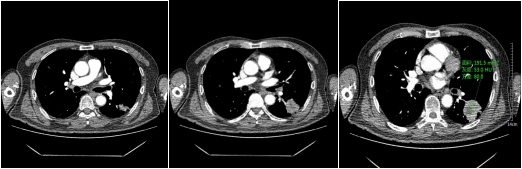

不同性质的结节,因为内部组织成份不同所以强化的方式不同,结节的供血方式也有不同,所以不同性质的肺结节,强化的方式也是不同。比如:急性期炎性肺结节因为组织成份多为肉芽组织,血管丰富,所以增强后明显强化,往往比平扫示强化程度高60HU以上;慢性期炎性肺结节,其主要成份示纤维组织,强化比较轻微,CT值较平扫多高20HU。

恶性实性结节,病变内含有肿瘤组织血管,强化程度不如急性炎性结节,增强CT扫描多升高20-60HU之间。

动脉期

静脉期